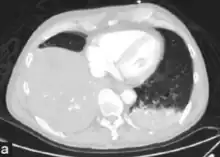

-

Chest X-ray pneumonia -

CT pneumonia -

X-ray pneumococcal osteomyelitis -

MRI pneumococcal osteomyelitis